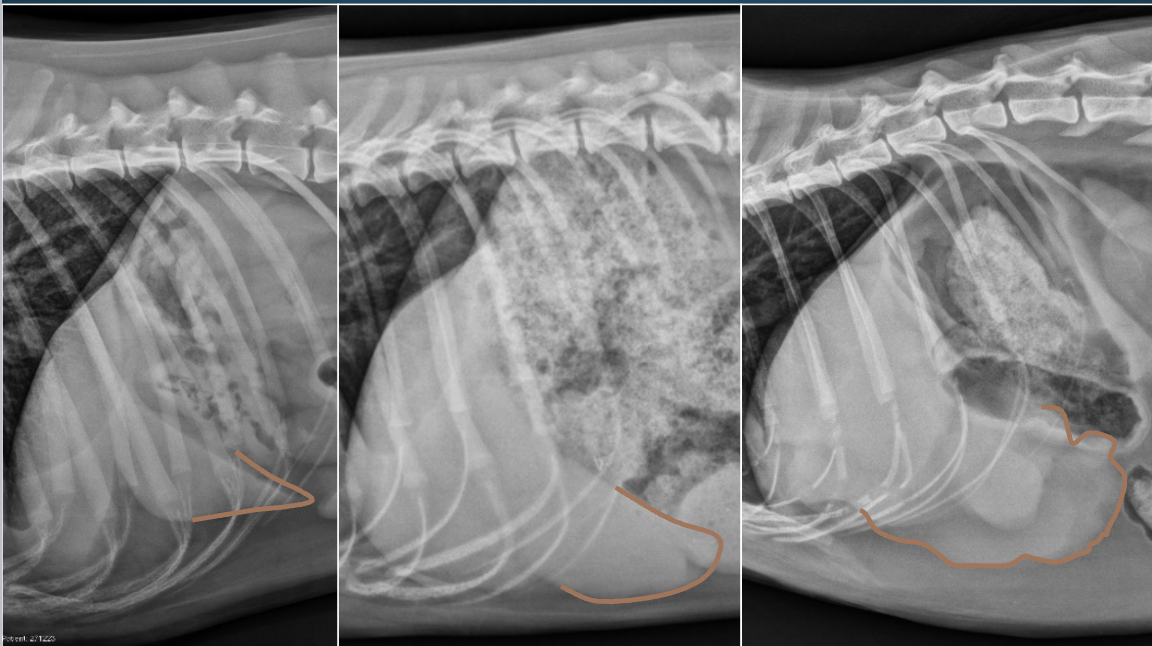

What is shown in these images?

A

*focal hepatomegaly:

-stomach displaced to the left on VD view

-right kidney is deviated

Q

Left: normal; normal margin

Middle: diffuse infiltrate; rounded margin

Right: focal mass; enlarged, lumpy margin